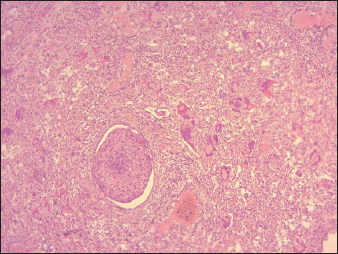

The most important histopathological lesions were observed in the lungs, intestines, spleen, and lymph nodes. The lungs had the most severe histopathological abnormalities, which were characterized by edema in the alveoli combined with fibrinous exudate infiltration of mononuclear cells and thickening of the interalveolar septa (Fig. 5), presence of syncytial cells (Fig. 5). Intestines revealed ulcerations of the intestinal mucosa in some areas, loss of intestinal villi with the intestinal crypts appearing clear and loss of epithelium, the lamina propria was infiltrated with Macrophages and lymphocytes, the duodenum, jejunum, and ileum showed extensive effusion of the submucosa with progressive thickening of the submucosal layer (Fig. 6). Degeneration and necrosis of glandular epithelial cells were also seen.

The lymphoid follicles in Peyer’s patches exhibited destruction, characterized by lympholysis (Fig. 6). MLNs showed severe congestion, hemorrhage, swelling, and depletion of lymphoid cells (Fig. 7). Additionally, other lesions are marked by the depletion of lymphocytes in the spleen, and histopathological changes in the heart, including congestion and hemorrhages. The thymus showed severe depletion of lymphocytes and severe congestion (Fig. 8). Furthermore, the liver showed severe congestion and hemorrhage with hepatocyte atrophy accompanied by the expansion of the sinusoidal spaces. The kidney exhibited slight glomerular atrophy, significant necrosis, and loss of epithelium in the renal tubules.

Fig. 7. Sheep, MLNs demonstrating severe lymphoid depletion mainly in the cortex with congestion and severe hemorrhage (100X, H&E).